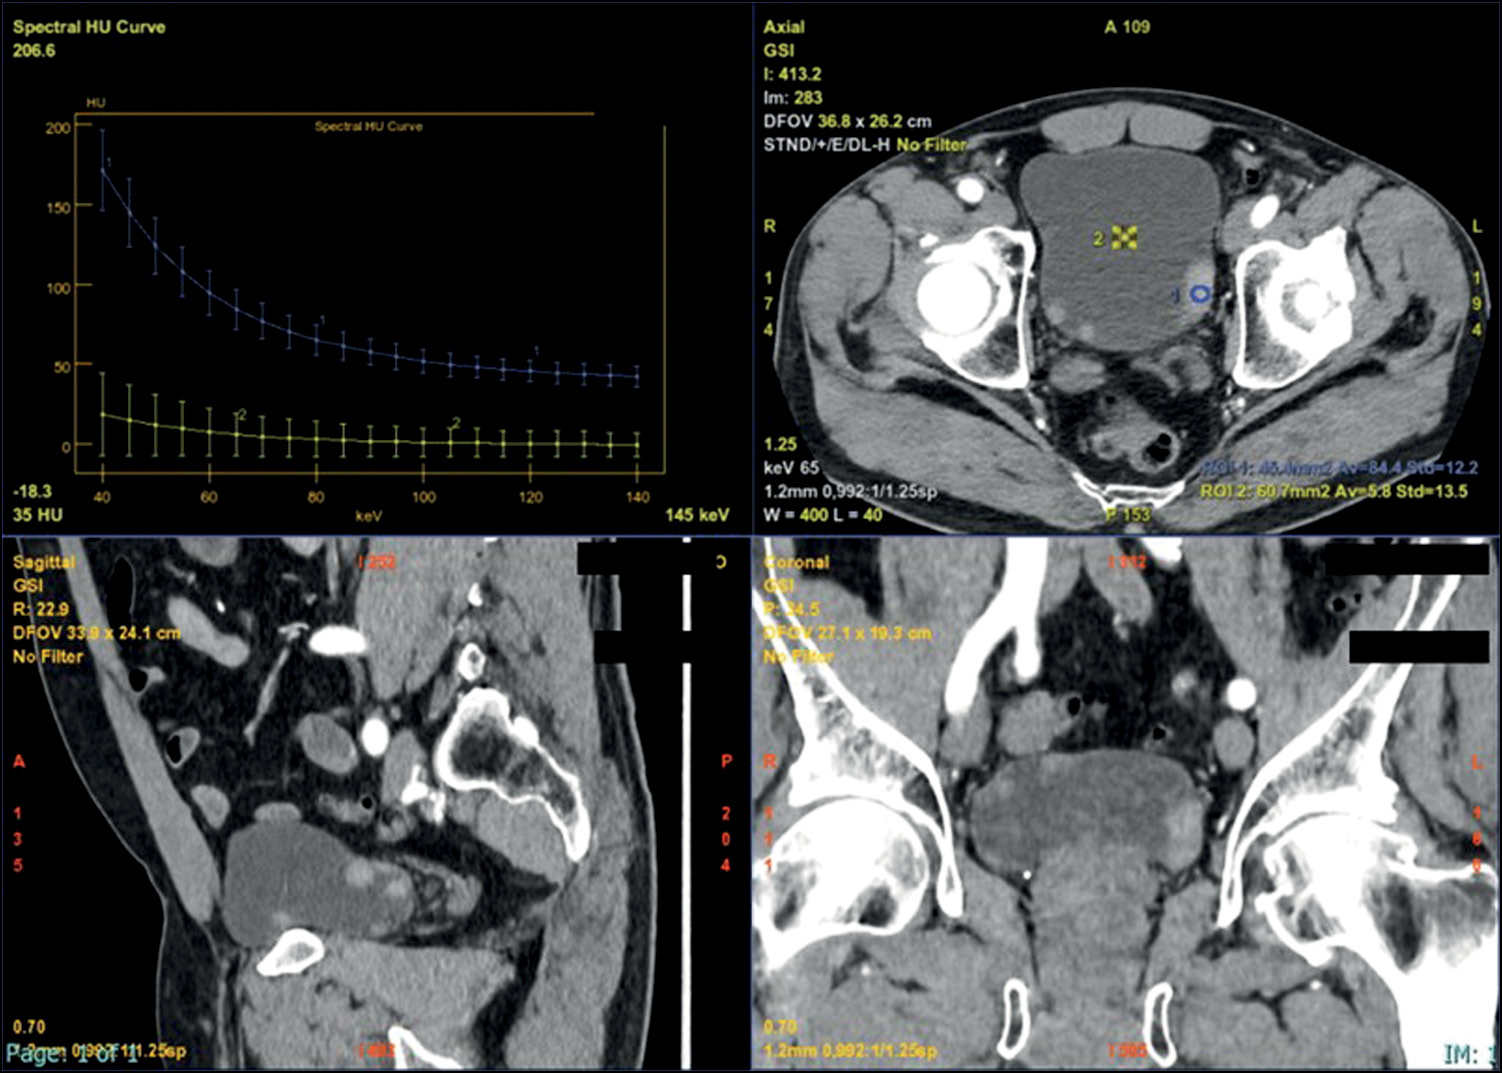

Considering the purpose of the examination such as the detection of a suspicious BCa or its staging, the most useful types of images are the virtual monochromatic (VMC), virtual non-contrast (VNC), iodine map, and atomic map.

VMC generates images similar to those of conventional single-energy CT considering quality; however, it provides more reliable attenuation values. The lower-energy kilovoltage setting can increase contrast among near structures, thanks to the high beam attenuation of iodine. Consequently, a parietal lesion is easier to recognize. The higher-energy kilovoltage setting can decrease noise and artifacts. The comparison between the two different kilovoltages settings, from VMC-acquired images, also produces a spectral attenuation curve, which is a function of energies. The latter is attributed to its properties, which are useful to improve lesion characterization.

VNC generates images “without contrast” by suppressing the iodine material uptake from scans acquired post-contrast. Therefore, VNC images are also known as iodine-removed images. Accordingly, the radiation dose could be reduced because the patient has not undergone the first unenhanced scan.

The iodine map is a material-specific image in opposition to the iodine-removed image, as iodine is selected and not suppressed to show all areas with iodine uptake. This image results in a color map that can quantify the iodine uptake expressing it in mg/mL. Moreover, it allows for distinguishing a vascularized lesion from a nonvascularized lesion considering the amount of iodine filling the aorta.

The effective atomic number map is a quantitative method for assessing material differentiation and evaluating attenuation variations as a function of energy [3].

The spectral curve, in the case of bladder wall thickening, shows a curve tending to increase from lower values of kilovoltage setting.

VMC images at low-energy kilovoltage settings generate better contrast of the tumor despite the nearby regions and increase the sensitivity in tumor detection. Moreover, by normalizing the iodine quantification to that of the aorta, in the nephrographic phase, this image type had increased specificity when a threshold of ≥3.0 mg/mL is reached and allows the differentiation of a vascular from a nonvascular lesion. The formula is as follows: |I| normalized=|I| lesion⁄|I| aorta [20, 21].

DECT advantages also concern BCa staging because iodine maps enable easier evaluation of the tumor infiltration of wall layers, including the muscular layer in differentiating an NMIBC from an MIBC and evaluating lymph node involvement and presence of metastases.

For treatment planning, the application of this technology may be crucial because it can better assess the relationship between the tumor and a vascular structure, with increased contrast obtained with the VMC at a lower kilovoltage setting, offering an important parameter (Fig. 3 and 4) [22].

Fig. 3. Multiplanar iodine map images showing different attenuations of multifocal masses, the main localized on the left posterior wall, with different Av values compared with the Av endoluminal value. The spectral curve (upper left side) allowed the characterization of materials because each material has a different attenuation curve.

Fig. 4. Multiplanar iodine map with coloring overlap showing different attenuations of multifocal masses, the main localized on the left posterior wall, with different Av values compared with the endoluminal Av value. The spectral curve (upper left side) allowed the characterization of materials because each material has a different attenuation curve.